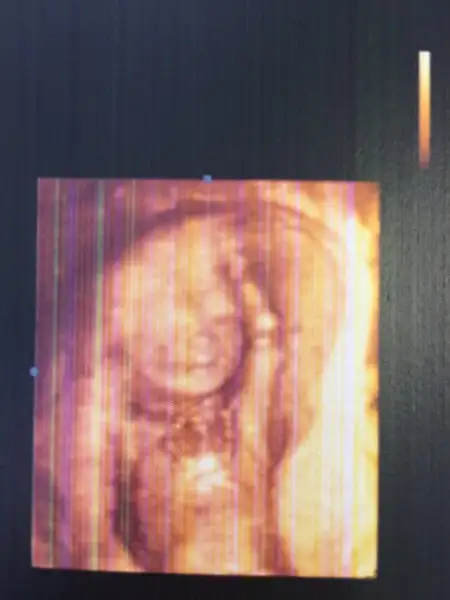

Maşalllahhhh 6. Ay güzelleri

bocugumu gordugum yok kız tirot kontrolü icin gldm her ay kan veriyorum.. doktor dioki suan gebelik yok demi bnde var dedm 19+4 hic belli degil diyo :)) anamm bı dünya asker vardi 40 50 tane hepsi dahiliyeye glmis kaldm iclernde... Kan vrcem smdi yarın sonucu gostercem